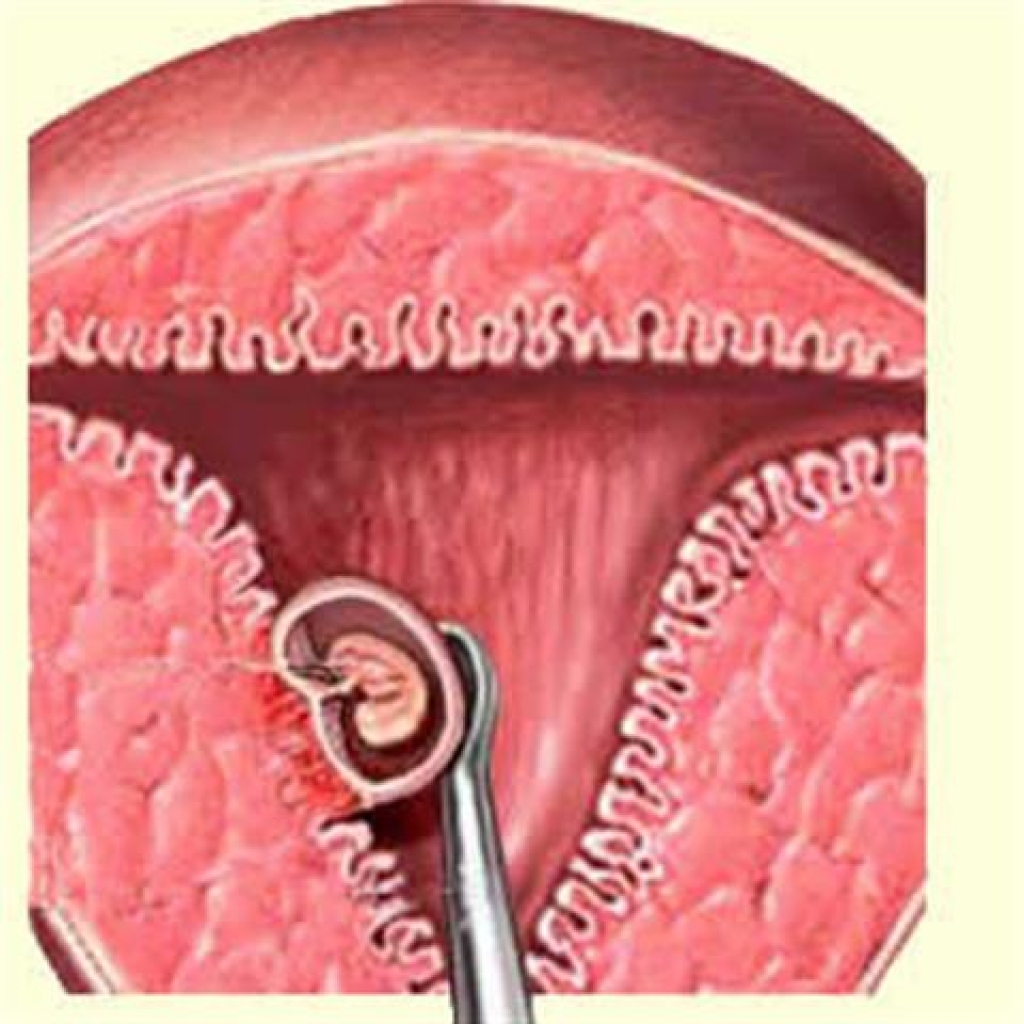

Анатомия женского организма: строение и функции матки

Раздел: Фотопуть к знанию